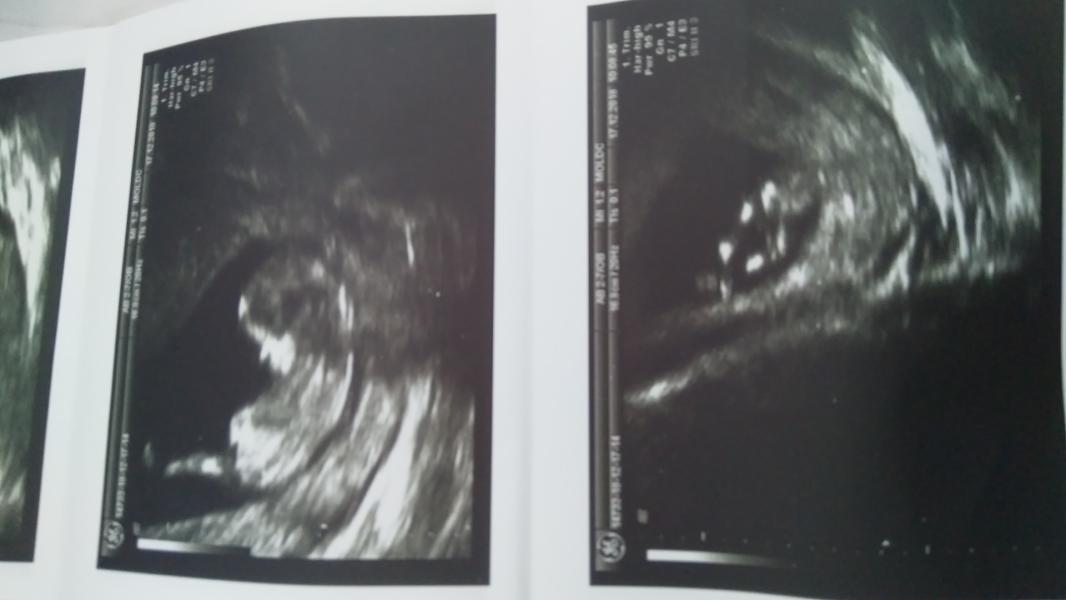

post image 2

post image 3

Вот мои фото)) видно кто будет?)

У меня просто все фото разные и на этом сроке почти всё одинаково. Так что я в шоке от фоток) всё смазано

Мальчик наверняка

Мне сегодня предложили, что будет мальчик)) но не точно)

Как носик хорошо виден)

Мне кажется мальчик